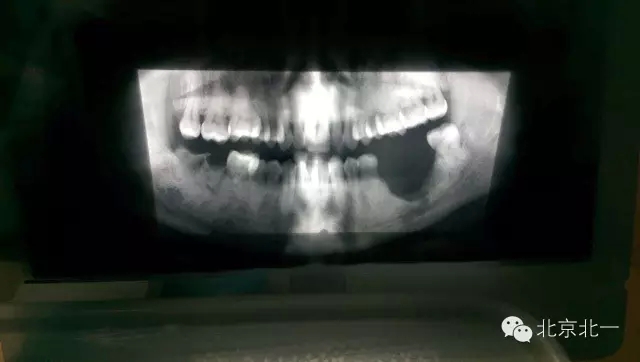

先看一例病例吧?拔牙前全景片。

圖二:拔牙后骨壞死,后被診斷為石骨癥,作為牙醫(yī)如果你還戰(zhàn)斗在拔牙一線,請正確認識石骨癥。(這是《北一微創(chuàng)拔牙班內(nèi)部教材》局部章節(jié)節(jié)選病例分析)